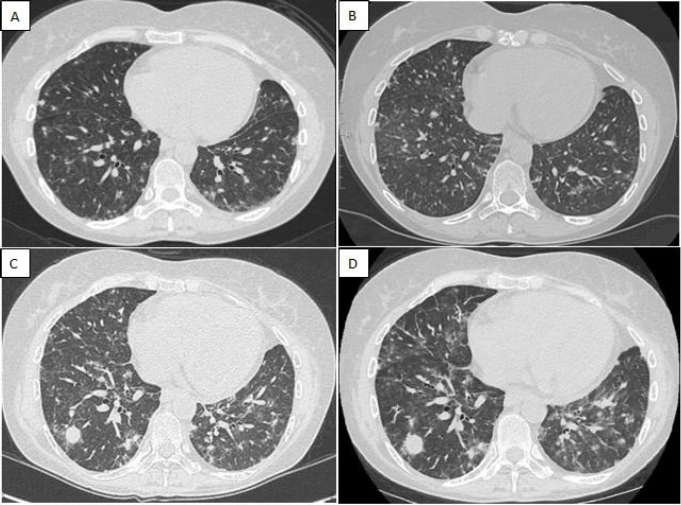

Given the clinical and instrumental (Fig. 2C and D) worsening, two pulmonary cryobiopsies were performed in 3 months: both confirmed an atypical nonspecific peribronchovascular lympho-histiocytic infiltrate. The progression of lung involvement led to partial respiratory failure requiring oxygen therapy.

(A) Lung CT shows bilateral parenchymal nodules with predominantly peribronchovascular distribution with slightly blurred margins, surrounded by ground glass areas; (B) Slight increase in micro nodularities and ground glass findings; (C) Appearance of major parenchymal consolidations with air crescent sign in the lateral segment of the right lower lobe; (D) Dimensional increase of the previously described consolidation with simultaneous worsening of the remaining findings.